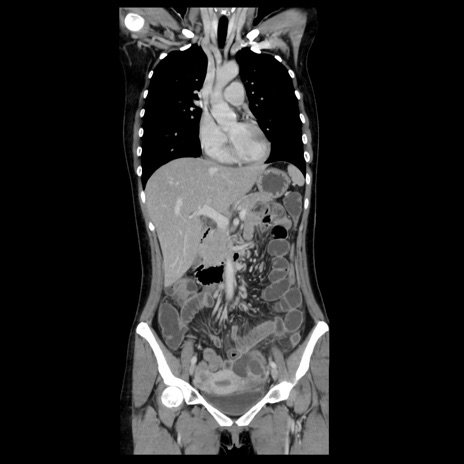

症例39(冠状断像)

【症例】40歳代女性

【主訴】上下腹部痛

【現病歴】2日目から下腹部痛あり。夜間は痛みで眠れなかった。昨日より上腹部痛と下痢が出現。臥位で痛みは軽快したため、休んでいた。本日になって臥位でも立位でも痛みが強くなってきたため救急要請。

【既往歴】子宮内膜症

【身体所見】部:平坦・軟、左上下腹部に圧痛あり、反跳痛あり。

【データ】WBC 21800、CRP 26.78

CT